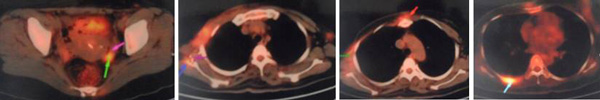

In June to August 2011, KT went to China for treatment. PET/CT scan showed the wound was 14 x 12 cm and the cancer had spread to her lymph nodes, lungs and bone. This was a Stage 4 cancer.

- Patient received iodine seeds implantation and cryosurgery in the lung,

- Iodine seeds implantation in the axillary fossa metastatic lymph nodes.

27 September 2011: Patient received iodine seeds implantation in the scapular region and left costal bone.